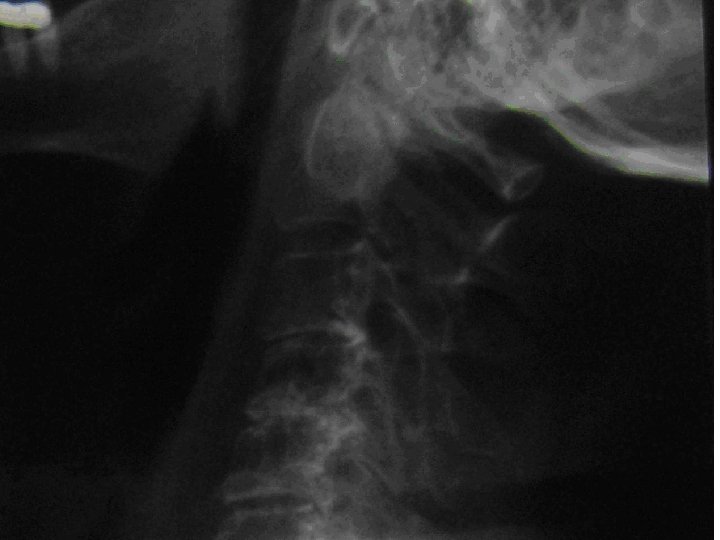

Radyoloji o o o Diz: Osteofit G 2 değişiklikler (OA) Omuz: NSİ Kalça: NSİ Servikal, Torakal ve Lomber: Dejeneratif değişiklikler Diğer?